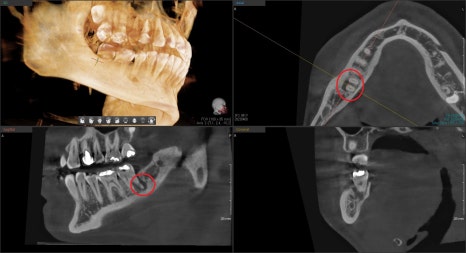

CT를 찍으면 더 확실하게 볼 수 있습니다.

뿌리 주변의 검은색으로 보이는 곳들이 염증으로 인한 치조골이 소실된 것입니다.

방사선 사진상에서도 뿌리에 금이 갔을 때 보이는

전형적인 치조골 소실 양상입니다.

빨간 원으로 표시된 부분을 보시면 육안으로도 보이는 명확한 crack line이 보이실 겁니다.

염증이 생긴 주된 원인은 뿌리 쪽 크게 진행된 금 주변으로 골 소실이 일어났을 것입니다.